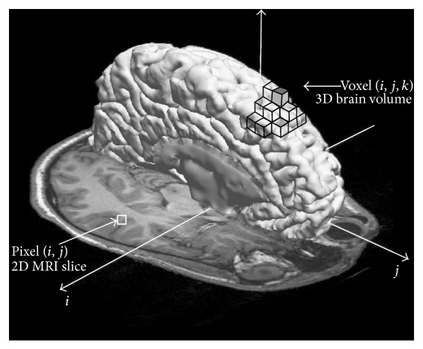

Clinical diagnostic and treatment decisions rely upon the integration of patient-specific data with clinical reasoning. Cancer presents a unique context that influence treatment decisions, given its diverse forms of disease evolution. Biomedical imaging allows noninvasive assessment of disease based on visual evaluations leading to better clinical outcome prediction and therapeutic planning. Early methods of brain cancer characterization predominantly relied upon statistical modeling of neuroimaging data. Driven by the breakthroughs in computer vision, deep learning became the de facto standard in the domain of medical imaging. Integrated statistical and deep learning methods have recently emerged as a new direction in the automation of the medical practice unifying multi-disciplinary knowledge in medicine, statistics, and artificial intelligence. In this study, we critically review major statistical and deep learning models and their applications in brain imaging research with a focus on MRI-based brain tumor segmentation. The results do highlight that model-driven classical statistics and data-driven deep learning is a potent combination for developing automated systems in clinical oncology.